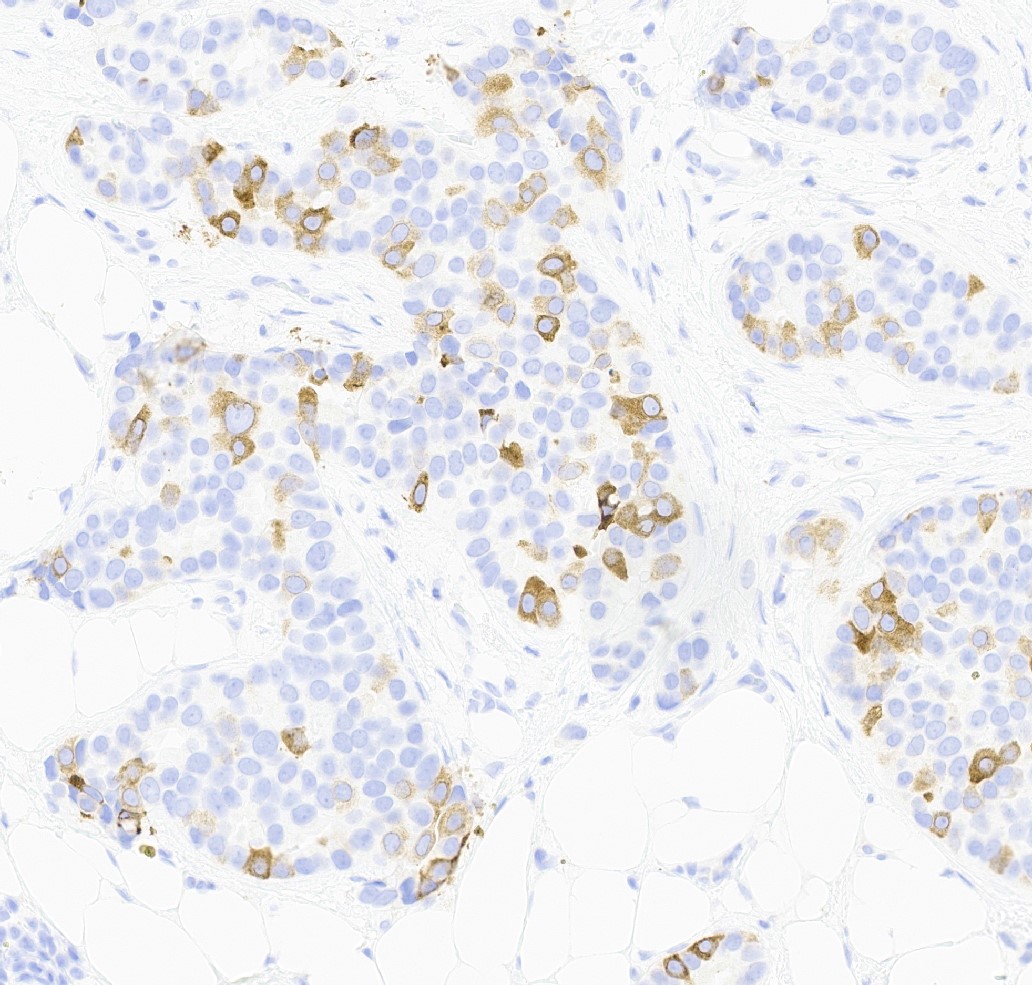

Microscopic (histologic) images

Contributed by Julie M. Jorns, M.D., Kristen E. Muller, D.O., Gary Tozbikian, M.D. and Emad Rakha, M.D.

Positive stains

- Luminal low molecular weight cytokeratins (CK8 / 18, CK19 and CK7 and pancytokeratins such as AE1 / AE3, CAM 5.2, MNF-116), EMA, E-cadherin, p120, ER (60 - 80%), PR (50 - 70%), HER2 (15 - 20%) (Am J Clin Pathol 2006;125:377)

- GATA3 (~91 - 100% of hormone receptor positive breast cancers, ~43 - 66% in triple negative breast cancer) (Hum Pathol 2014;45:2225, Hum Pathol 2015;46:1829)